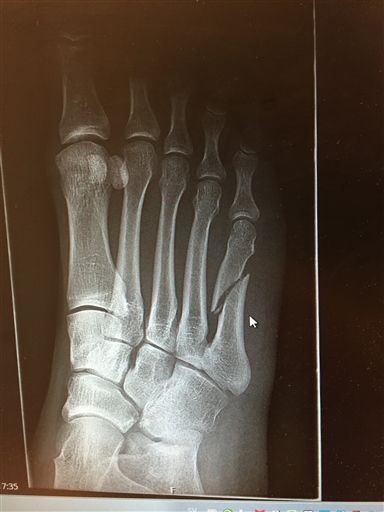

Bild uppladdad av Mike Lourey

I helgen var olyckan framme då jag hoppade studsmatta på Turbo i Uppsala. Landade lite fel i ett hopp och knäckte femte metatarsalbenet. Benet är helt av ungefär halvvägs, med ett snett brott.

Som det är nu är det gips i minst 4 veckor. Reponeringen blev inte helt bra enligt akutläkaren, men blev uppringd av en ortoped idag som tycke att det såg bra ut så operation är inte aktuellt i dagsläget. Bilden visar brottet före gips/reponering, har ingen bild hur det blev efteråt.